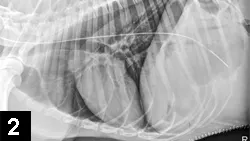

Figure 2. Radiograph confirming appropriate postoperative placement of a nasogastric tube in a dog.

• Nasogastric tubes allow aspiration of gastric contents, which may decrease nausea and vomiting and help prevent aspiration pneumonia (See Figures 2 and Figure 3).